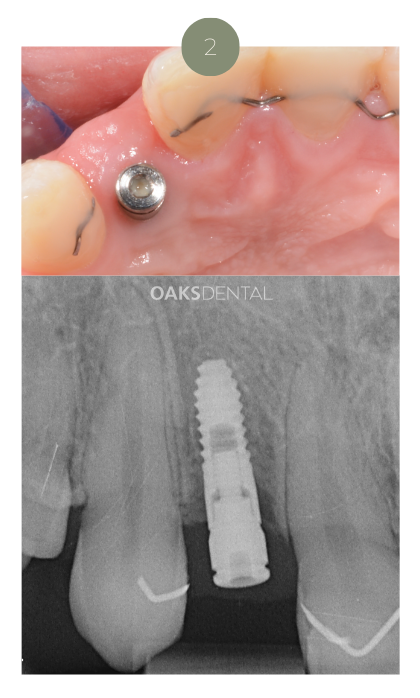

2. Surgical Implant Placement

Under local anaesthetic, the implant is gently placed into the jawbone.

If needed, bone grafting material may be used to support stability.

Most patients describe this step as surprisingly comfortable — often easier than a tooth extraction.